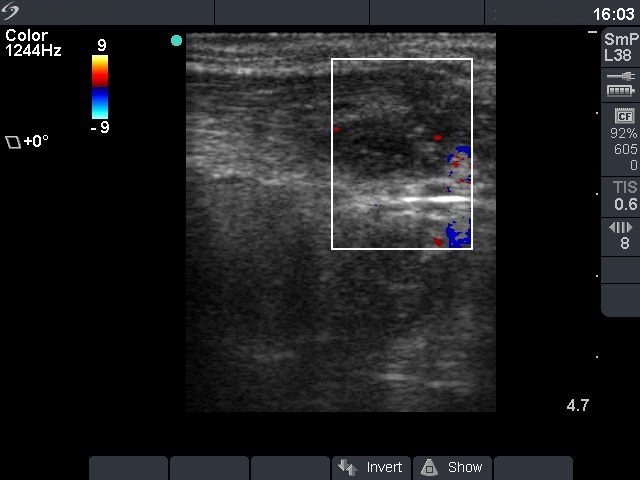

Before sclerotherapy (first row):

Clinical presentation: a 48-year-old man with repeatedly aspirated and recurred thyroid cyst causing complaints.

Palpation: there was a large nodule in the isthmic part of the thyroid.

Ultrasound. The size of the lesion was 38x28x39 mm (width x depth x length).FNAC resulted in a benign lesion.